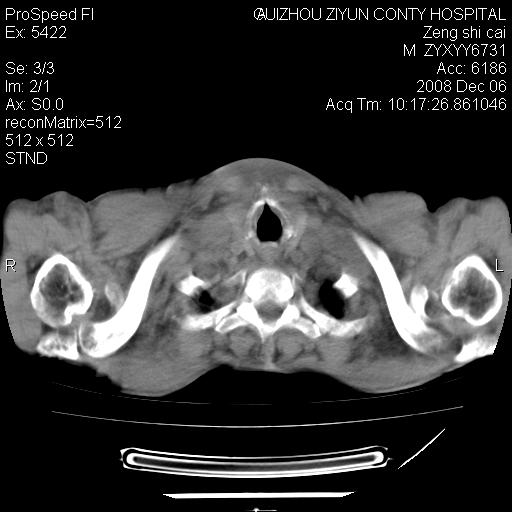

标题: CT16961:M、71岁,咳嗽半年,无血痰;胸片示右肺占位。 [打印本页]

标题: CT16961:M、71岁,咳嗽半年,无血痰;胸片示右肺占位。

右肺癌并纵隔淋巴结及胸膜转移可能性大

右肺癌并纵隔淋巴结及胸膜转移。建议气管镜

右肺纵隔型肺癌伴纵隔淋巴结及胸膜转移!

右肺纵隔型肺癌伴纵隔淋巴结转移!双侧胸水!

1)考虑右肺上叶纵隔型肺癌伴纵隔淋巴结转移。2)心包积液,双侧胸腔积液。

右肺癌并纵隔淋巴转移,腹膜后转移可能性大,两侧胸腔积液

右肺癌并纵隔淋巴结及胸膜心包转移,好多团团点点,看得有点想吐

右肺上叶纵隔型肺癌伴纵隔淋巴结转移。心包积液,双侧胸腔积液。

右上肺癌并纵隔淋巴结及胸膜转移。

建议强化!主要鉴别是淋巴瘤与肺癌淋巴结转移。

右肺纵隔型肺癌伴纵隔淋巴结及胸膜转移